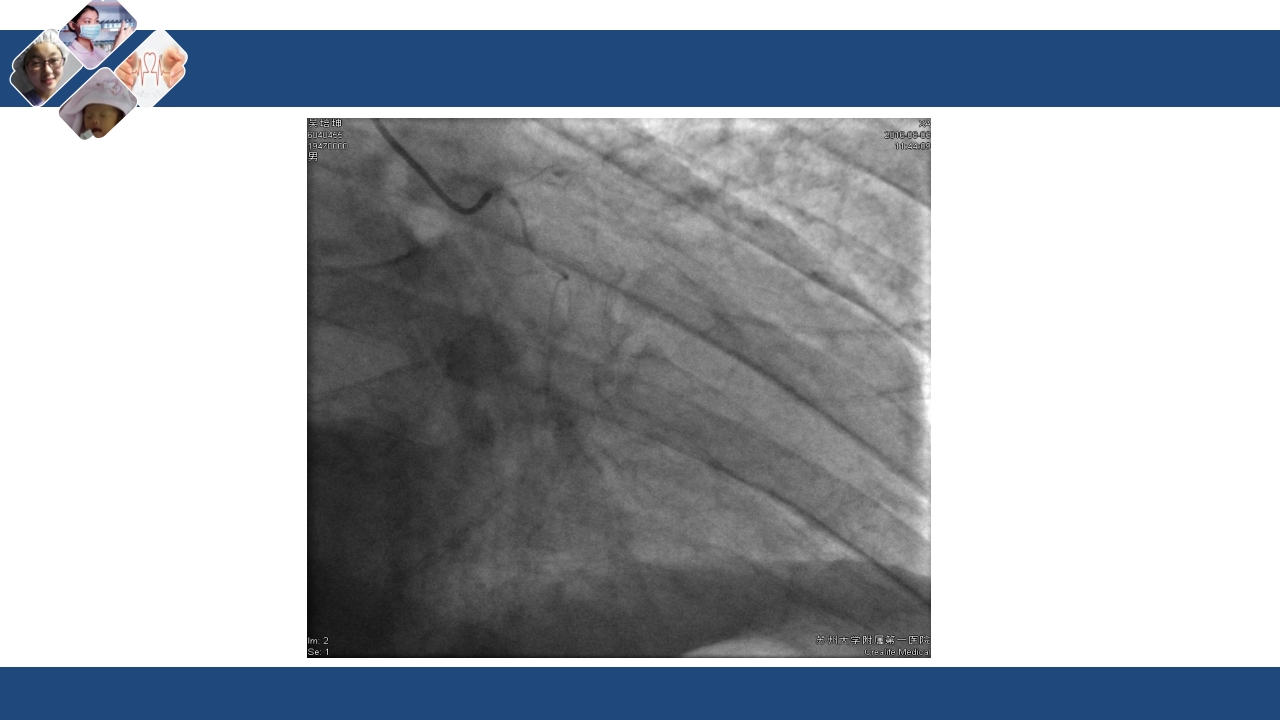

心肌梗死合并心源性休克 医院:xxx 时间:xxx 休克 是由于各种原因导致的急性循环障碍,使周围组织血流 灌注量严重不足(微循环障碍),以致各重要生命器官机 能代谢发生严重障碍的全身性病理生理过程。 休克的病因: 心源性 低血容量性 感染性 过敏性 神经内分泌性 创伤性 休克的病因: 心源性 低血容量性 感染性 过敏性 神经内分泌性 创伤性 心源性休克(cardiogenic shock) 心源性休克系指由 心室泵功能损害而 导致的休克综合征, 是心泵衰竭的极期 表现。 由于心排血功能衰 竭,不能维持其最 低限度的心输出量, 导致①血压下降, ②重要脏器和组织 供血不足,引起③ 全身性微循环功能 障碍 从而出现一系列缺 血、缺氧、代谢障 碍及重要脏器损害 为特征的病理生理 过程。...